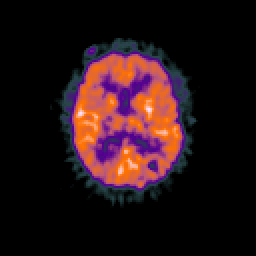

Glioma overlay -- Slice #66

[Home][Help][Clinical] Slice 66